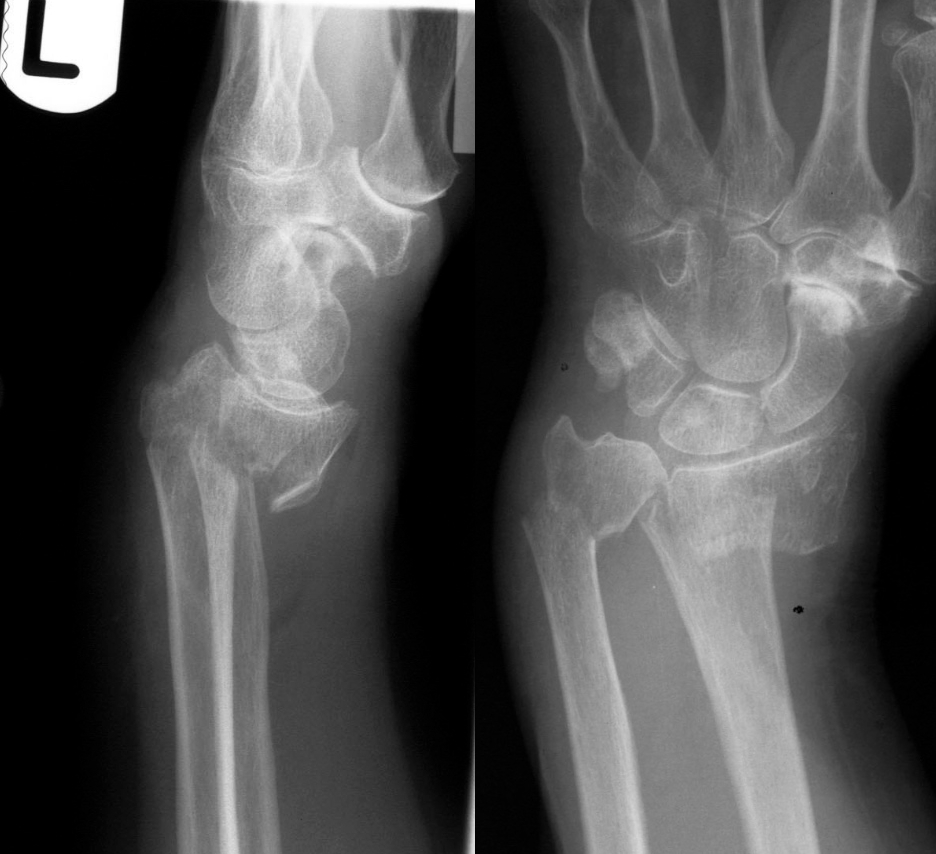

- Рентгенография. Является базовым исследованием, позволяет обнаруживать обычные и поднадкостничные переломы, но может быть малоинформативной при эпифизеолизе. В зависимости от уровня повреждения производится рентгенография костей предплечья, лучезапястного либо локтевого сустава в двух проекциях.

Для точной диагностики перелома лучевой кости со смещением необходимо выполнить рентгеновское исследование. Рентген обеспечивает возможность получения точного изображения скелета, его структуры и состояния.

При этом медицинский работник оценивает правильность анатомической структуры, орентацию костей по отношению друг к другу и наличие возможных изменений.

Рентгеновские снимки

обеспечивают четкое изображение плотных структур, таких как кости. Поскольку кисть, запястье, предплечье и локоть могут быть повреждены при падении на вытянутую руку, врач может назначить рентген локтя и запястья, а также предплечья, чтобы определить степень травмы.